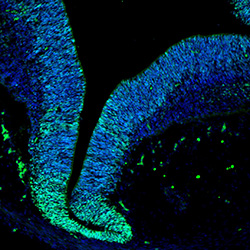

An in vivo and in vitro spatiotemporal profile of human midbrain development

An anatomical analysis of the developing human midbrain from 6 post-conceptional weeks (PCW) to 22 PCW reveals increased tissue complexity, characterized by the emergence of dopaminergic nuclei, as highlighted by immunofluorescence analysis for tyrosine hydroxylase (TH).

6PCW human midbrain